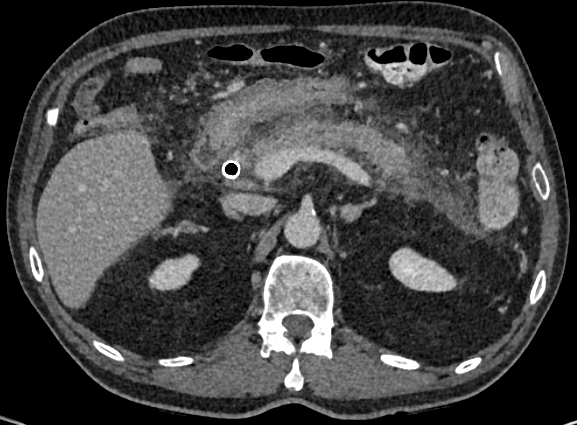

3. Pancreatitis post ERCP